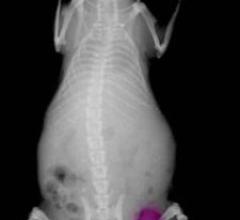

September 19, 2007 - MEDRAD announced the availability of the 3.0T Prostate eCoil MR Endorectal Coil compatible with magnetic resonance (MR) scanners made by Philips and Siemens, increasing patient access to prostate MR, an emerging imaging procedure for early diagnosing and staging of prostate cancer.

September 18, 2007 - The ARIA Breast Imaging System, developed by Advanced Imaging Technologies, is a single, safe ...

September 19, 2007 - The Medipattern Corp., developer of computer-aided diagnosis (CAD) technologies for medical imaging ...